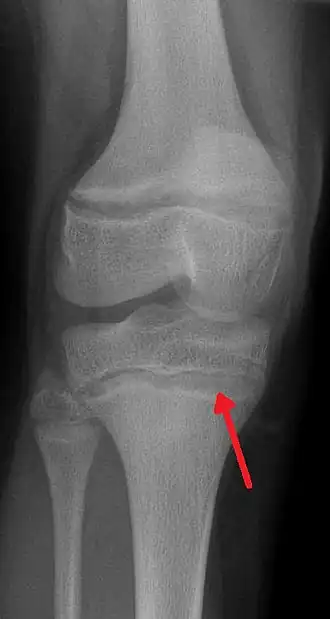

| Raio X mostrando a característica linha de chumbo na metáfise da tíbia. | |